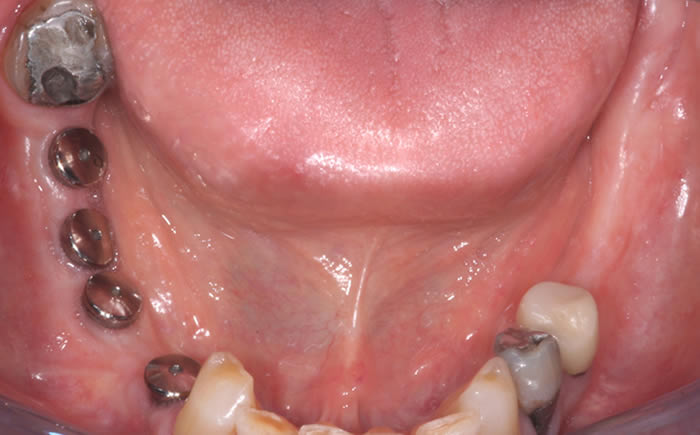

More back teeth replaced by dental implants

Case Three (2 images)

Case Four (4 images)

Case Five (4 images)

Case Six (8 images)

Case Seven (4 images)